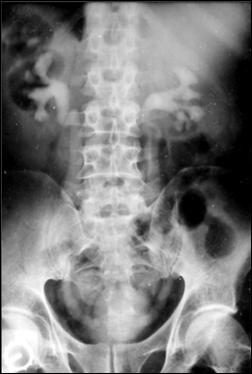

Diagnosticul diferential cu tuberculoza urogenitala

Vezica urinara are contururi greu delimitabile pe cistografie si pacientul are ureterohidronefroza bilaterala.

Figura 59. Vezica urinara "crispata", cu ureterohidronefroza bilaterala. |